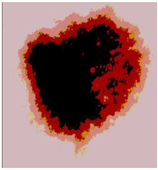

![]() | ![]() | ![]() | ![]() |

| Img1 | --- Pixel Intensity (0–255) ---> | ||

| Img2 | --- Pixel Intensity (0–255) ---> | ||

| Img3 | --- Pixel Intensity (0–255) ---> | ||

| Img4 | --- Pixel Intensity (0–255) ---> | ||

| Img5 | --- Pixel Intensity (0–255) ---> | ||

| Img6 | --- Pixel Intensity (0–255) ---> | ||

| Img7 | --- Pixel Intensity (0–255) ---> | ||

| Img8 | --- Pixel Intensity (0–255) ---> | ||

| Img9 | --- Pixel Intensity (0–255) ---> | ||

| Img10 | --- Pixel Intensity (0–255) ---> | ||